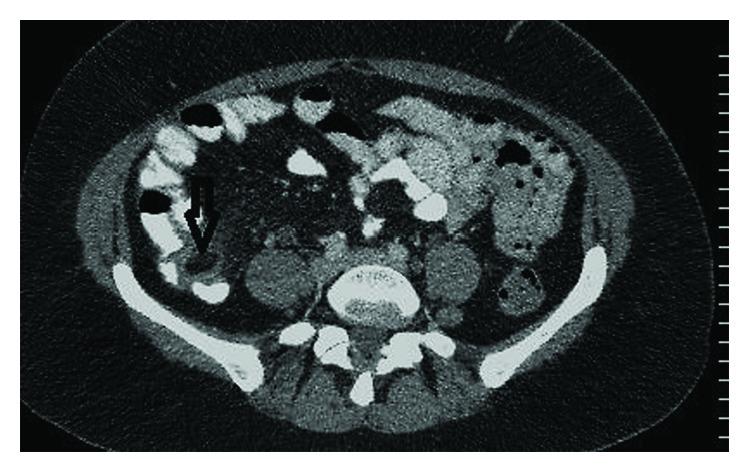

A 46-year-old female presented to our emergency department (ED) with a 2-day history of right lower abdominal pain which was associated with nausea and anorexia. Abdominal examination revealed tenderness in the right iliac fossa (RIF) with rebound tenderness and a localized guarding. Urine dipstick was normal, and the pregnancy test was negative. Her laboratory investigations were significant only for a CRP of 16.6. A presumptive clinical diagnosis of acute appendicitis was suggested based on the given history and relevant physical signs. However, an abdominal computed tomography (CT) scan revealed an epiploic appendagitis of the caecum with a normal-looking appendix. She was managed conservatively and responded well and was discharged after 2 days in good health. Though being a relatively rare case of acute localized right-sided lower abdominal pain, caecal epiploic appendagitis should be considered as one of the differential diagnoses with the final diagnosis reached usually by the radiological findings due to the nonspecific nature of clinical and laboratory features.

一名46岁女性因右下腹痛2天前来我院急诊科就诊,伴有恶心和厌食。腹部检查发现右髂窝压痛,有反跳痛和局限性肌紧张。尿试纸检查正常,妊娠试验阴性。她的实验室检查仅C反应蛋白为16.6有意义。根据所给病史和相关体征,初步临床诊断为急性阑尾炎。然而,腹部计算机断层扫描(CT)显示盲肠的网膜附件炎,阑尾外观正常。她接受了保守治疗,反应良好,2天后健康出院。尽管盲肠网膜附件炎是急性局限性右下腹痛的相对罕见病例,但由于临床和实验室特征的非特异性,应将其视为鉴别诊断之一,最终诊断通常通过影像学检查得出。